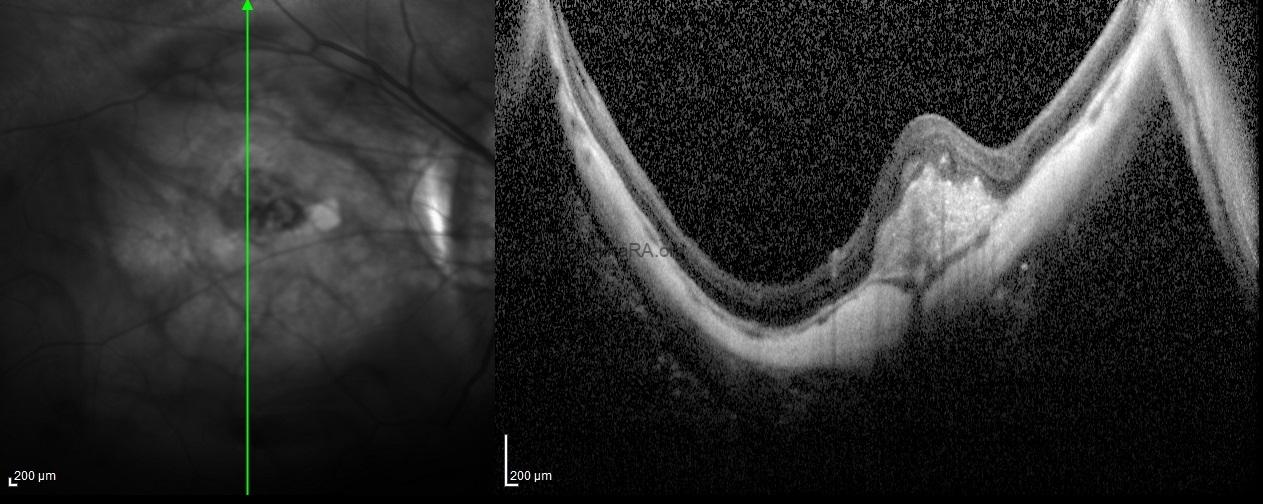

Spectral-domain optical coherence tomography showed the choroidal neovascular membrane scar without any subretinal or intraretinal fluid in additon to posterior staphyloma in the right eye. For the left eye, the OCT-scan passing throught the lesion under the optic disc exhibited an intrachoroidal space with a hyporeflective appearance below the normal plane of retinal pigment epithelium with normal Bruch’s membrane and retinal layers over the lesion.

Peripapillary intrachoroidal cavitation is a yellow-orange lesion which located at the outer border of the myopic conus. First described as a localized detachment of the retinal pigment epithelium, its intrachoroidal location was later revealed, justifying its current name. It can be seen with other myopic complications such as posterior staphyloma, but its pathogenesis is not still clear to. Although it has been considered a benign condition, most eyes with intrachoroidal cavitaiton demonstrate visual field defects leading to diagnostic uncertainty as these deficits resemble those seen in glaucomatous eyes. With the advances in optical coherence tomography, high optic nerve sheath traction forces during eye movements in highly myopic eyes have been suggested as promoters of intrachoroidal cavitaiton.